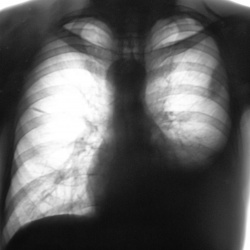

ВИЧ - носитель" направлен на рентгеновское исследование органов грудной полости с диагнозом "ПНЕВМОНИЯ".Пневмония произведено стандартное рентгенологическое исследование.Рентгенограммы в...

29.10.2012 - 19:44